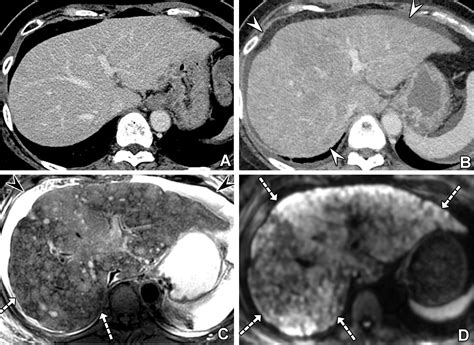

Abdominal CT Scan Provides detailed cross-sectional images to identify lesion size and location.

MRI with Contrast Highly sensitive; often used to differentiate benign lesions from metastases.

💡 Note: While imaging is highly effective, not all liver lesions are cancerous; some may be benign cysts or hemangiomas, which is why clinical correlation is always necessary.